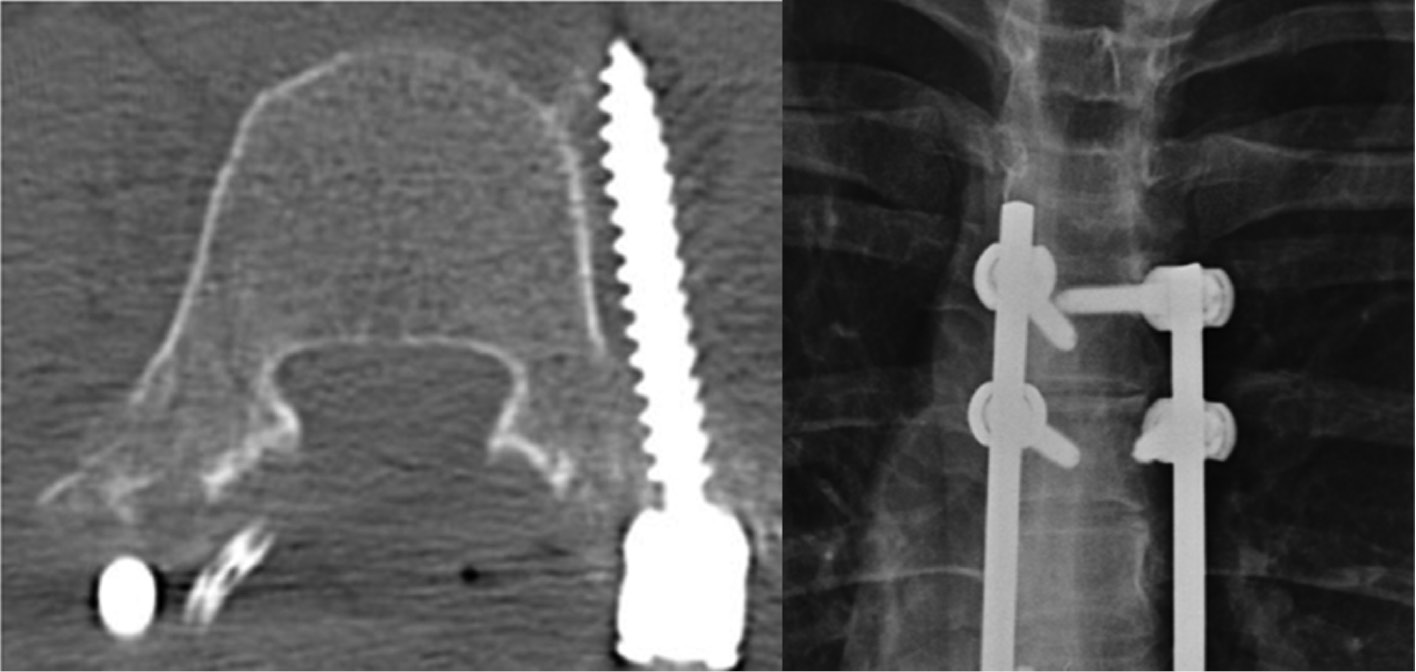

Although uncommon with modern techniques, pseudoarthrosis is another potential source of pain following PSF. Pseudoarthrosis has been defined as “the absence of bony fusion 1 year” post PSF.14 Pseudoarthrosis typically manifests months to years after initial PSF as axial or radicular pain or implant failure (broken or loosened implants) but can also be asymptomatic (Figure 2). The reported incidence of pseudoarthrosis varies among studies. One systematic review involving 16,938 pediatric patients who underwent spinal surgery for AIS reported a 1.4% occurrence of pseudoarthrosis following spinal deformity surgery.15 Overall, some risk factors for pseudoarthrosis include insufficient or poor-quality bone grafting, inadequate stability of the fusion construct, and smoking. Imaging studies, such as x-ray and CT are used in diagnosis but are less sensitive than direct surgical exploration. Several studies including one by Quon et al. advocate for the use of PET imaging over CT imaging in diagnosing nonunion following spinal fusion.16

Figure 2. Two years after PSF this patient had worsening in her chronic back pain. The radiographs demonstrated rod fracture and CT confirmed pseudarthrosis.

jposna20220030_fig2.jpg